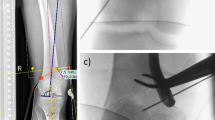

Forty-eight ulnar Synbone models (Synbone, Malans, Switzerland) of the same laterality, size, and density were used in this study. Mayo type IIA olecranon fracture models were created by an osteotomy. The models were then randomly divided in two groups: TBW group (n = 16), IM-TBW group (n = 16) and DSTBW group (n = 16). In the DSTBW group,the fractures were stabilized through methods reported in our previous study16 : the fractures were reduced and fixed by two Ding’s screws (4.0 mm in diameter); two 18-gauge metal wires were passed through the holes on the tail of Ding’s screws separately and used to make the figure-of-eight wiring between the 2.0-mm hole on the ulnar shaft and the two Ding’s screws(Fig. 2A). In the TBW group, the fractures were stabilized by the traditional K-wires and tension band fixation24,25 (Fig. 2B). In the IM-TBW group, the fractures were stabilized by the IM and tension band fixation26 (Fig. 2C).The position of internal fixation was determined by X-ray technique for each model in all groups.

A Synbone Mayo type IIA fractures model demonstrates the fixation technique in DSTBW (A), TBW (B) and IM-TBW (C). (A, B, C) Posteroanterior and lateral views and X-ray of each group.